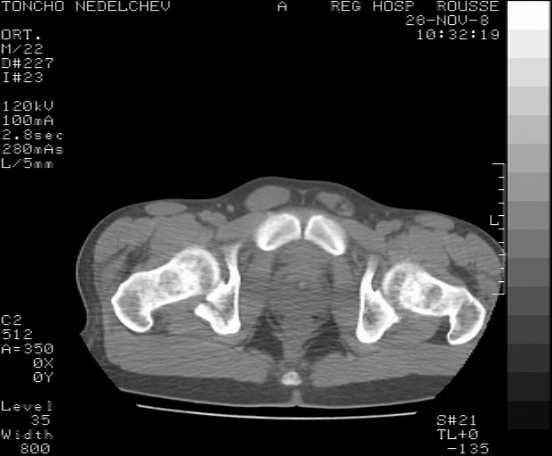

[Ortho] Acetabular fracture

Here are some more axial images. What is your opinion as for the timing of the operative treatment?